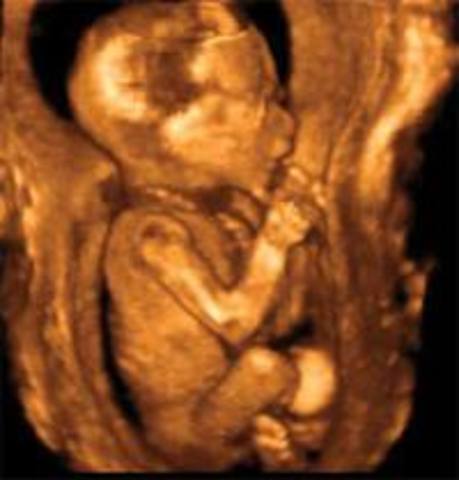

After 10 weeks the mother can have her first ultrasound.

After 23-24 weeks the fetus’ eyes are fully formed even though it is too dark for the fetus to see

After 24 weeks the fetus’ senses kick in.